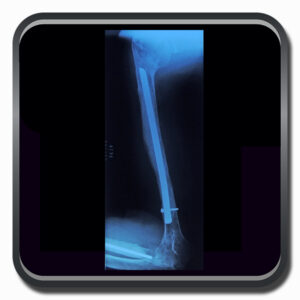

Algumas Cirurgias Complexas realizadas por profissionais da COFIB: